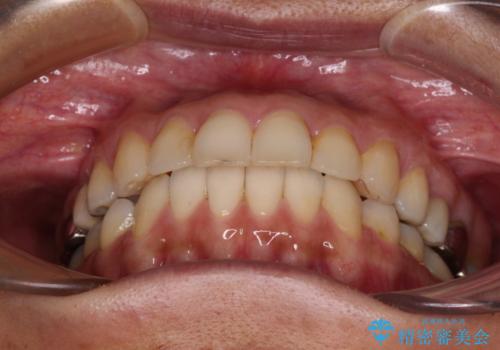

後戻りは軽微であったため、インビザライン・ライトにて歯列を整えました。

矯正治療後には、左下奥歯の症状がないことを確認し、セラミッククラウンにて補綴治療を行うこととしました。

矯正治療後のレントゲン写真では、根尖部に認められた病変(骨の溶けていた像)は消失していることが分かりました。